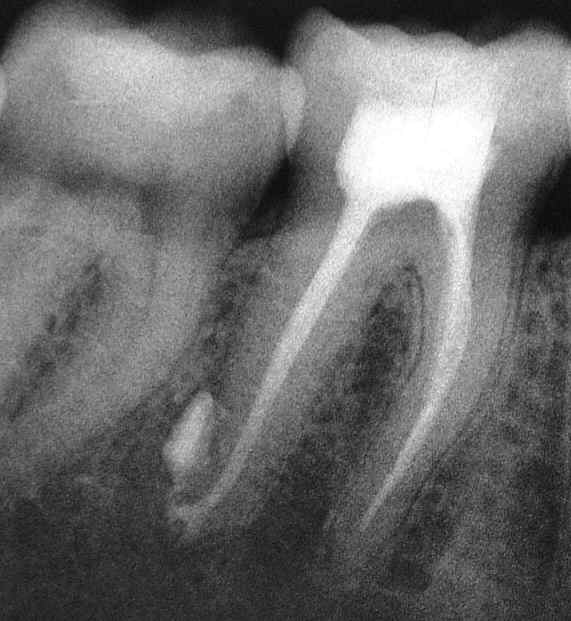

Durch Fistelung komplizierter, kombiniert endodontisch-parodontologischen Fall, wie er täglich vorkommt und genau so regelmäßig zur Extraktion gelangt. Dabei ist ein solcher Befund mit Geduld sehr einfach und routinemäßig auszuheilen.

Deutlich sieht man die abgefüllte Fistel und die nach sorgfältiger, geduldiger Desinfektion mit ChKM langsame knöcherne Ausheilung in Richtung Restitutio ad integrum unter Resorption des überpressten Sealers und den „wundersamen“ Knochengewinn. Knochen ist eben ausgesprochen langsam in seinem Stoffwechsel, so dass die Resorption unter röntgenologisch knochendichter Ausheilung nur sehr langsam erfolgt. Mit Blick auf den Verlauf kann man dieses Krankheitsbild dennoch mit großer Sicherheit als ausgeheilt bezeichnen.